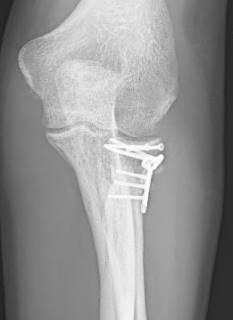

Rekonstruktion des Radiusköpfchens durch Schrauben und Plättchen

Eine Fraktur mit nur einem verschobenen Bruchstück von mehr als 2 mm (Typ-2-Fraktur nach Mason) wird meist durch Kleinstfragment-Schrauben oder Plättchen versorgt. Dieses Verfahren wird als Osteosynthese bezeichnet und kann minimalinvasiv durchgeführt werden.

Das verschobene Knochenfragment wird dabei in seine ursprüngliche anatomische Lage reponiert (gerichtet) und fixiert. Eine Stufenbildung der Gelenkfläche soll so vermieden werden, um die Funktion des Radiusköpfchens im Ellenbogengelenk optimal wiederherzustellen. Schrauben oder Plättchen müssen bei korrekter Lage später nicht zwingend entfernt werden. Begleitverletzungen der Bänder können ebenfalls während des Eingriffes versorgt werden.

Rekonstruktion des Radiusköpfchens durch winkelstabile Platten

Auch komplexe Frakturen mit mehreren Bruchstücken und begleitender Verrenkung (Luxation) können durch eine Osteosynthese kopferhaltend therapiert werden. Dazu werden spezielle winkelstabile Radiusköpfchenplatten verwendet, die die einzelnen Fragmente stabil fixieren.